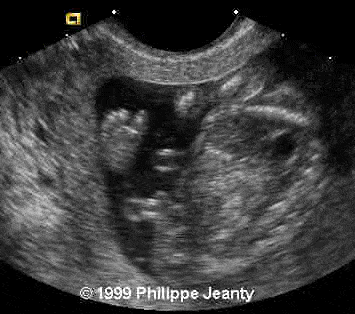

• abnormal cardiac axis

The cardiac axis is a little offset and the interventricular septum incomplete

Very few, however, made the most crucial observation: the great disproportion between the head and abdomen. That disproportion is very typical of triploidy (see the lecture on aneuploidy for another example) and I know of no other conditions where such a big difference exist without a concomitant intracranial anomaly such as hydrocephaly, or teratomas… Of course, one of you will come up with a great differential diagnosis and then we will learn even more !

Teaching point: A head much greater than the abdomen is a strong sign of triploidy.